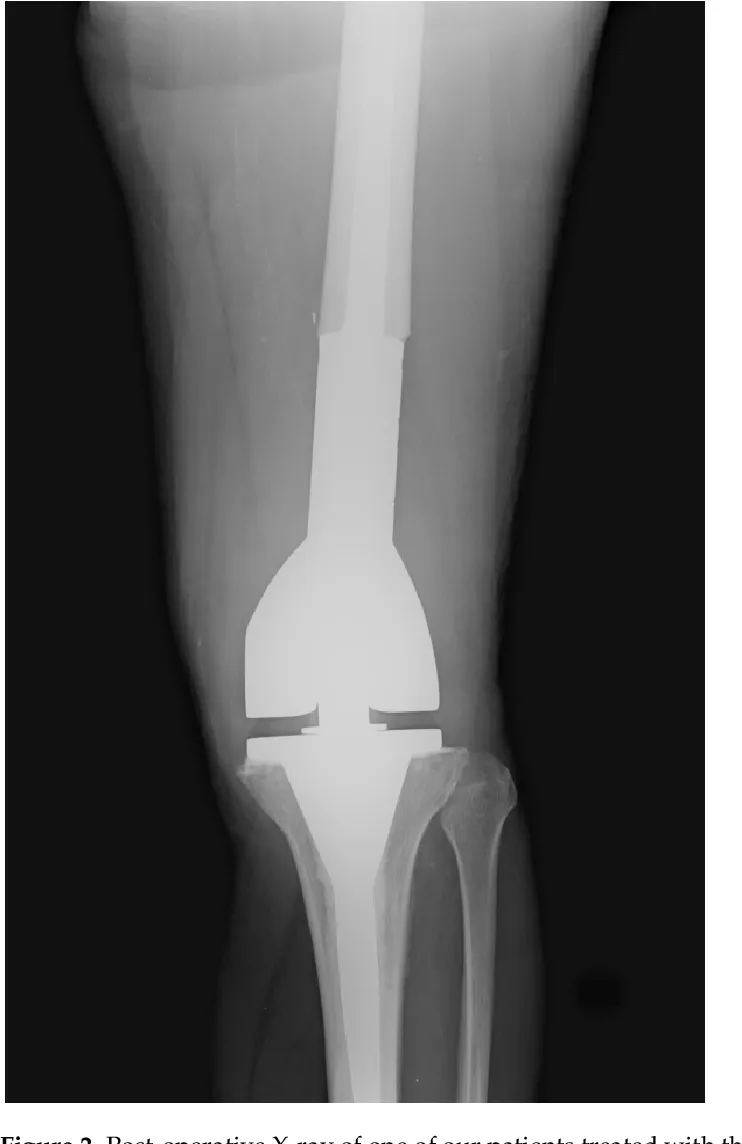

طرف اصطناعي ضخم معياري يستخدم لاستبدال عظم الفخذ البعيد بالكامل بعد الاستئصال الجراحي الواسع للساركوما العظمية.

استبدال الفخذ البعيد (بدلة الأورام): دليل طبي شامل

يعتبر استبدال الفخذ البعيد (Distal Femoral Replacement - DFR) باستخدام بدلة الأورام إجراءً جراحيًا متقدمًا وحاسمًا في مجال جراحة العظام، وخصوصًا في علاج أورام العظام الخبيثة التي تصيب الجزء السفلي من عظم الفخذ. يهدف هذا الإجراء إلى استئصال الجزء المصاب من العظم مع الحفاظ على الطرف، وذلك بتعويضه ببدلة صناعية متخصصة. لقد أحدثت هذه التقنية ثورة في علاج مرضى أورام العظام، حيث سمحت بالحفاظ على وظيفة الطرف وتحسين جودة حياة المرضى بشكل كبير، بدلًا من اللجوء إلى البتر الذي كان الخيار الوحيد في الماضي.

تعد بدلة الأورام المستخدمة في استبدال الفخذ البعيد مصممة خصيصًا لتلبية احتياجات المرضى الذين يعانون من فقدان كبير في العظام نتيجة لاستئصال الأورام. تتميز هذه البدلات بمرونتها وقدرتها على التكيف مع مختلف التشريحات ومتطلبات الاستئصال الجراحي. يتطلب هذا الإجراء تخطيطًا دقيقًا وتنفيذًا جراحيًا فائقًا، بالإضافة إلى برنامج تأهيل مكثف لتحقيق أفضل النتائج الوظيفية.